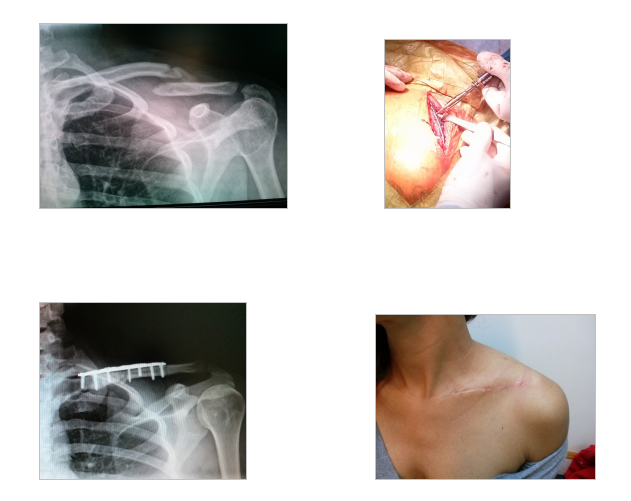

En este caso el paciente de 40 años que práctica tenis, acude con la fractura y se realiza la osteosíntesis con placa anatómica de clavícula, vemos el control favorable a los 15 días y la cicatrización de la paciente al mes de operada.